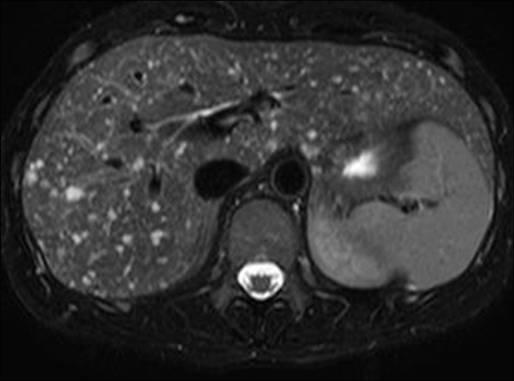

Hamartoma đường mật

» Thông tin: Nam giới – 34 tuổi.

» Lâm sàng: Kiểm tra sức khỏe.